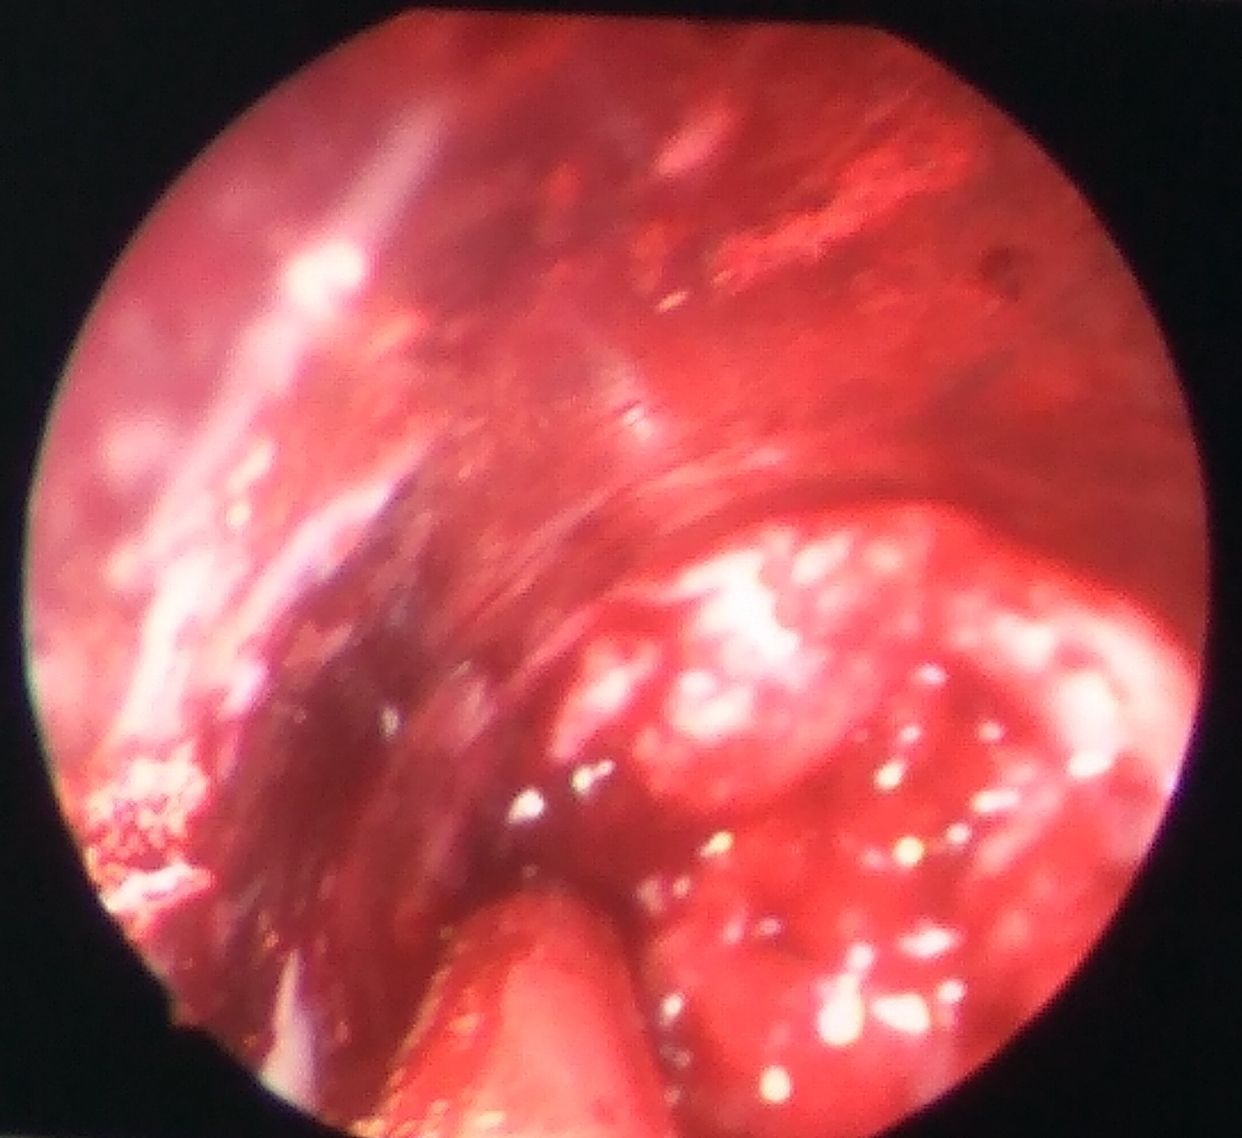

血肿清除过程中